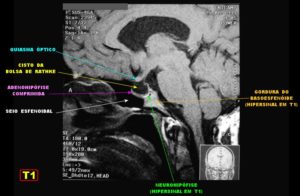

При визуализации киста кармана Ратке представляет хорошо отграниченное, срединно расположенное, не усиливающиеся образование между передней и промежуточной долями гипофиза. 40% кист имеет интраселлярную локализацию, 60% — имеют супраселлярный компонент. Чисто супраселлярная локализация встречается редко.

Магнитно-резонансная томография

Кисты кармана Ратке почти всегда имеют гомогенную интенсивность МР сигнала, в то время как кистозные краниофарингеомы и аденомы с кровоизлиянием имеют гетерогенный сигнал. [9] Уровни жидкости подразумевают кровоизиляние в анамнезе. Хотя кисты кармана Ратке не имеют характерных только для данной нозологии МР признаков. Большинство кист можно отнести к двум группам:

- Кисты кармана Ратке с низкой интенсивностью МР сигнала на Т1 взвешенных изображениях и высокой интенсивностью сигнала на Т2 взвешенных изображениях,

- Кисты кармана Ратке с высокой интенсивностью МР сигнала на Т1 взвешенных изображениях и различной интенсивностью МР сигнала на Т2 взвешенных изображениях

В первой группе содержимое кисты серозное и имеет сигнальные характеристики соответствующие ЦСЖ. Во второй группе содержимое кист богато мукополисахаридами, которые считаются продуктами муцин-продуцирующих клеток в стенке кисты.

В редких случаях повышенный сигнал на Т1 взвешенных изображениях сочетается с низким МР сигналом на Т2 взвешенных изображениях за счет комбинации факторов включающих наличие мукополисахаридов, продуктов распада гемоглобина, высокого содержания холестерола и сушенных клеточных масс.

Сигнальные характеристики в соответствии с содержимым кисты:

- T1

- 50% гиперинтенсивные (высокое содержание мукополисахаридов)

- 50% гипоинтенсивные

- T2

- 70% гиперинтенсивные

- 30% изо- и гипоинтенсивные

- T1 C+

- отсутствие контрастного усиления

- может присутствовать тонкое кольцевидное усиление прилежащей ткани гипофиза за счет сдавления [3,4]

- может присутствовать тонкое кольцевидное усиление отражающее метаплазию эпителия